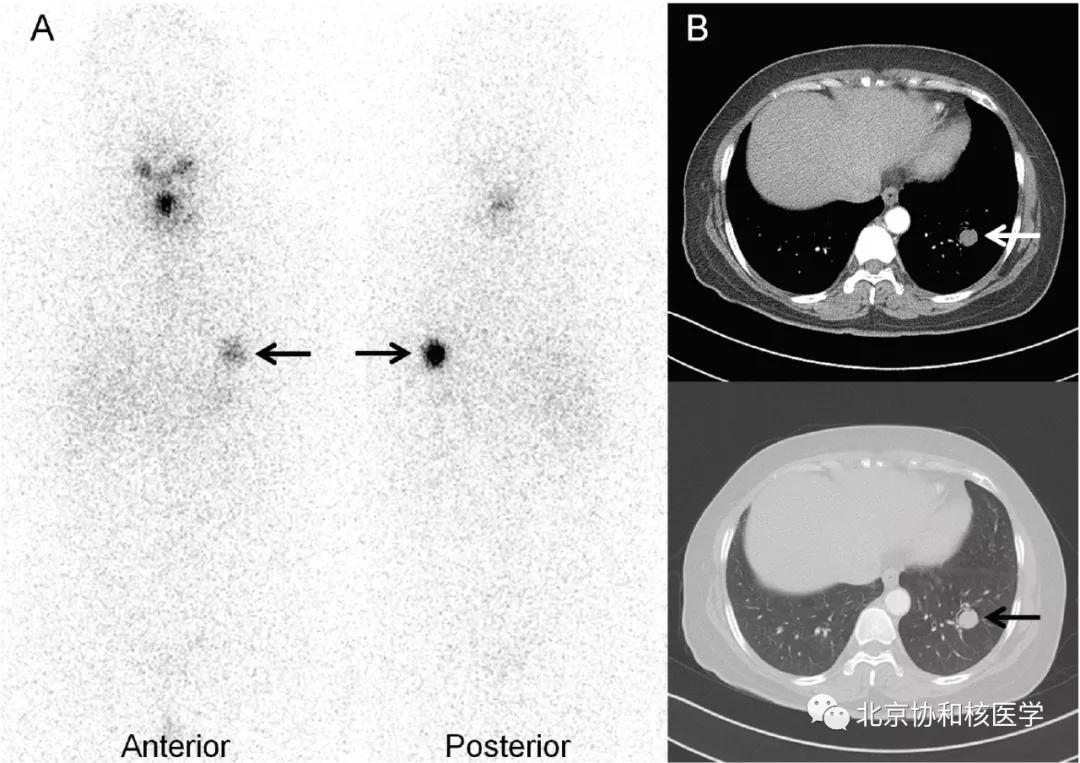

肺鳞癌所致碘摄取(后位图像),同时可见颈部甲状腺残余病灶:

63岁女性,甲状腺癌病史,肺内不典型分支杆菌感染所致碘摄取: